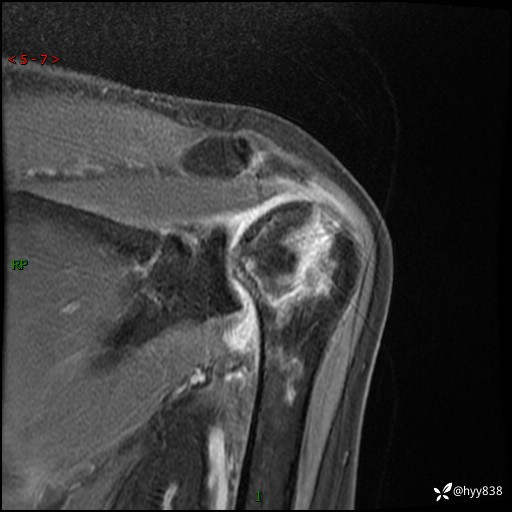

肱骨正侧位片

肱骨MRI平扫(axi T1WI+cor T2WI-fs)+CE-fs(COR+SAG)